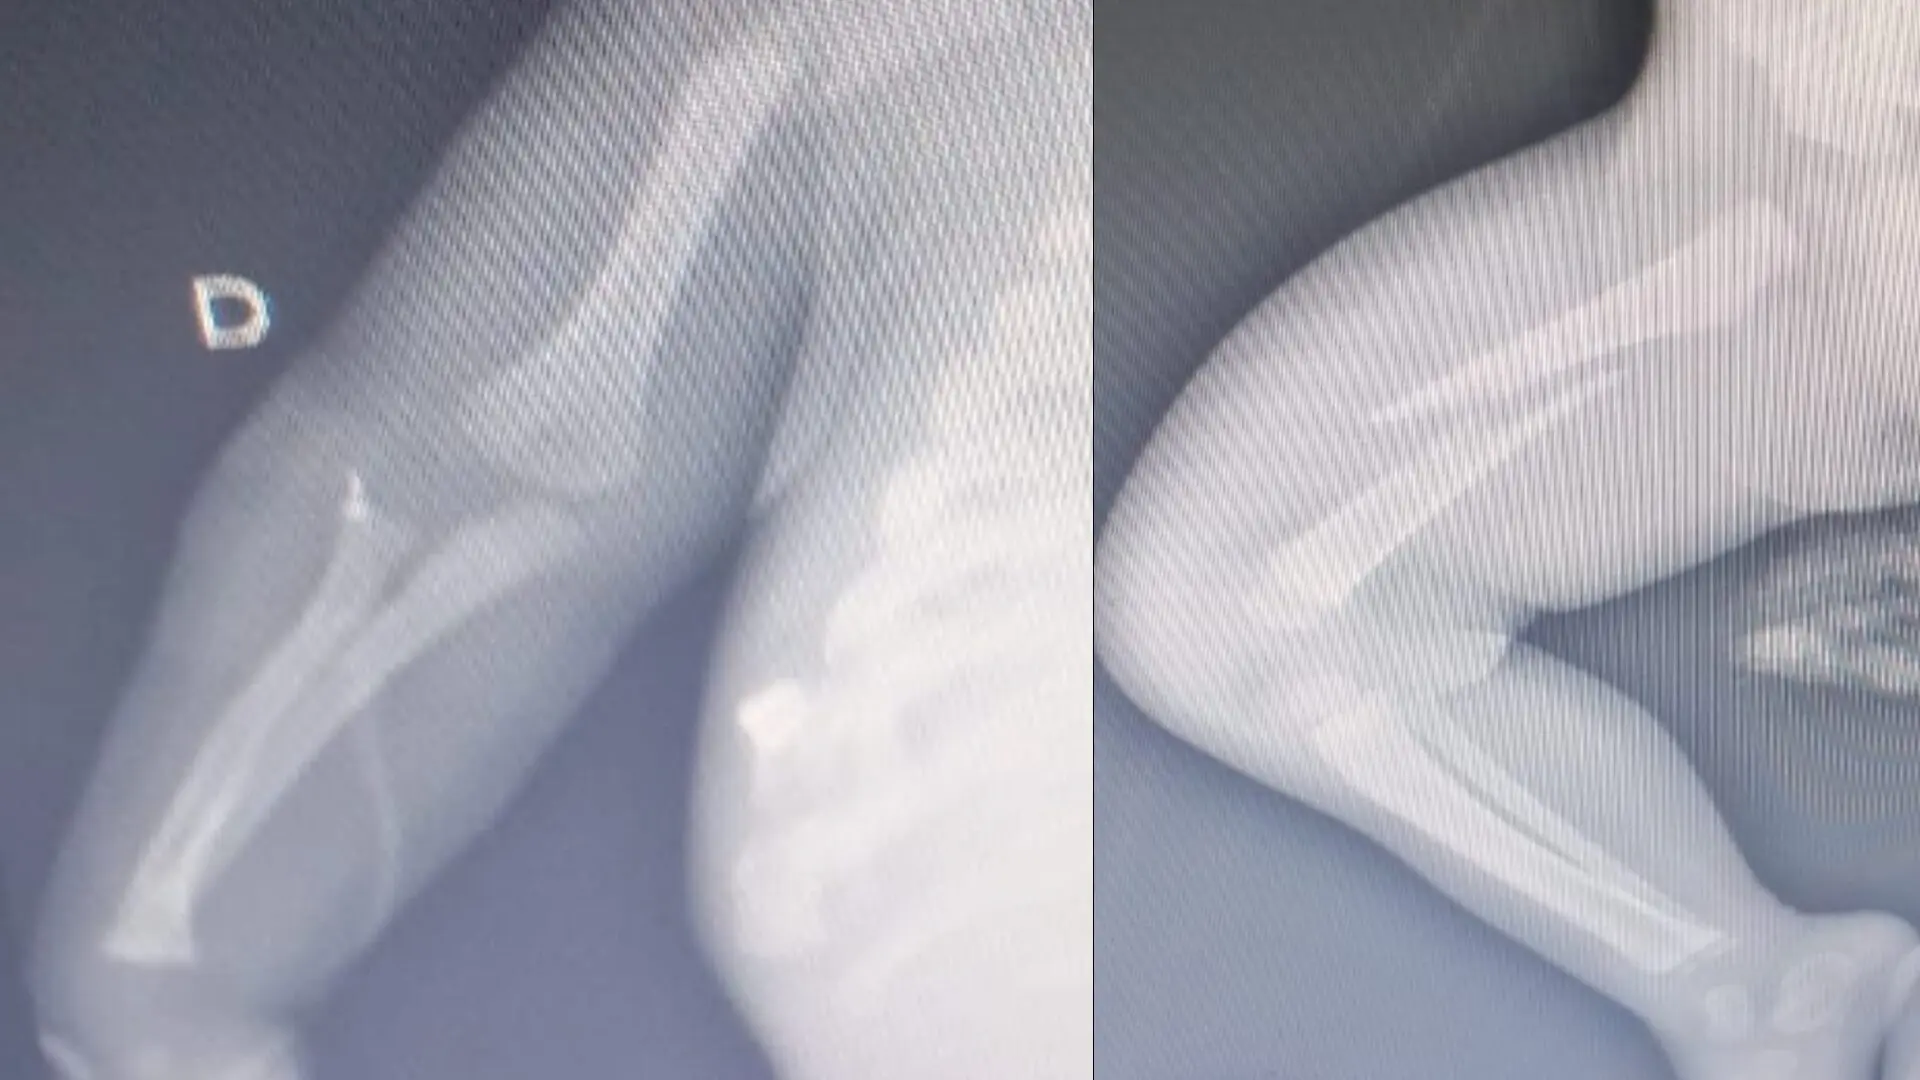

De acordo com a conselheira tutelar que atendeu a ocorrência, o bebê foi levado inicialmente ao Hospital Humanitária pelo pai, mas, devido à gravidade das lesões, foi transferido com urgência para a Santa Casa de Limeira. Os médicos que atenderam a criança identificaram escoriações e hematomas por todo o corpo, além de fraturas nos braços, fêmur e costelas, estas últimas já em estágio inicial de consolidação.

A conselheira tutelar esteve na casa onde o rapaz e o bebê moravam, na Rua Henrique Oliviere, no Jardim Nossa Senhora de Fátima, que foi cedida por um amigo dele, e constatou que a cama do local era baixa, o que não justificaria os ferimentos graves apresentados pela criança. Imagens do quarto e exames de raio-X foram anexados ao processo, que agora inclui também a requisição para exame de corpo de delito emitida pelo Instituto Médico Legal (IML).